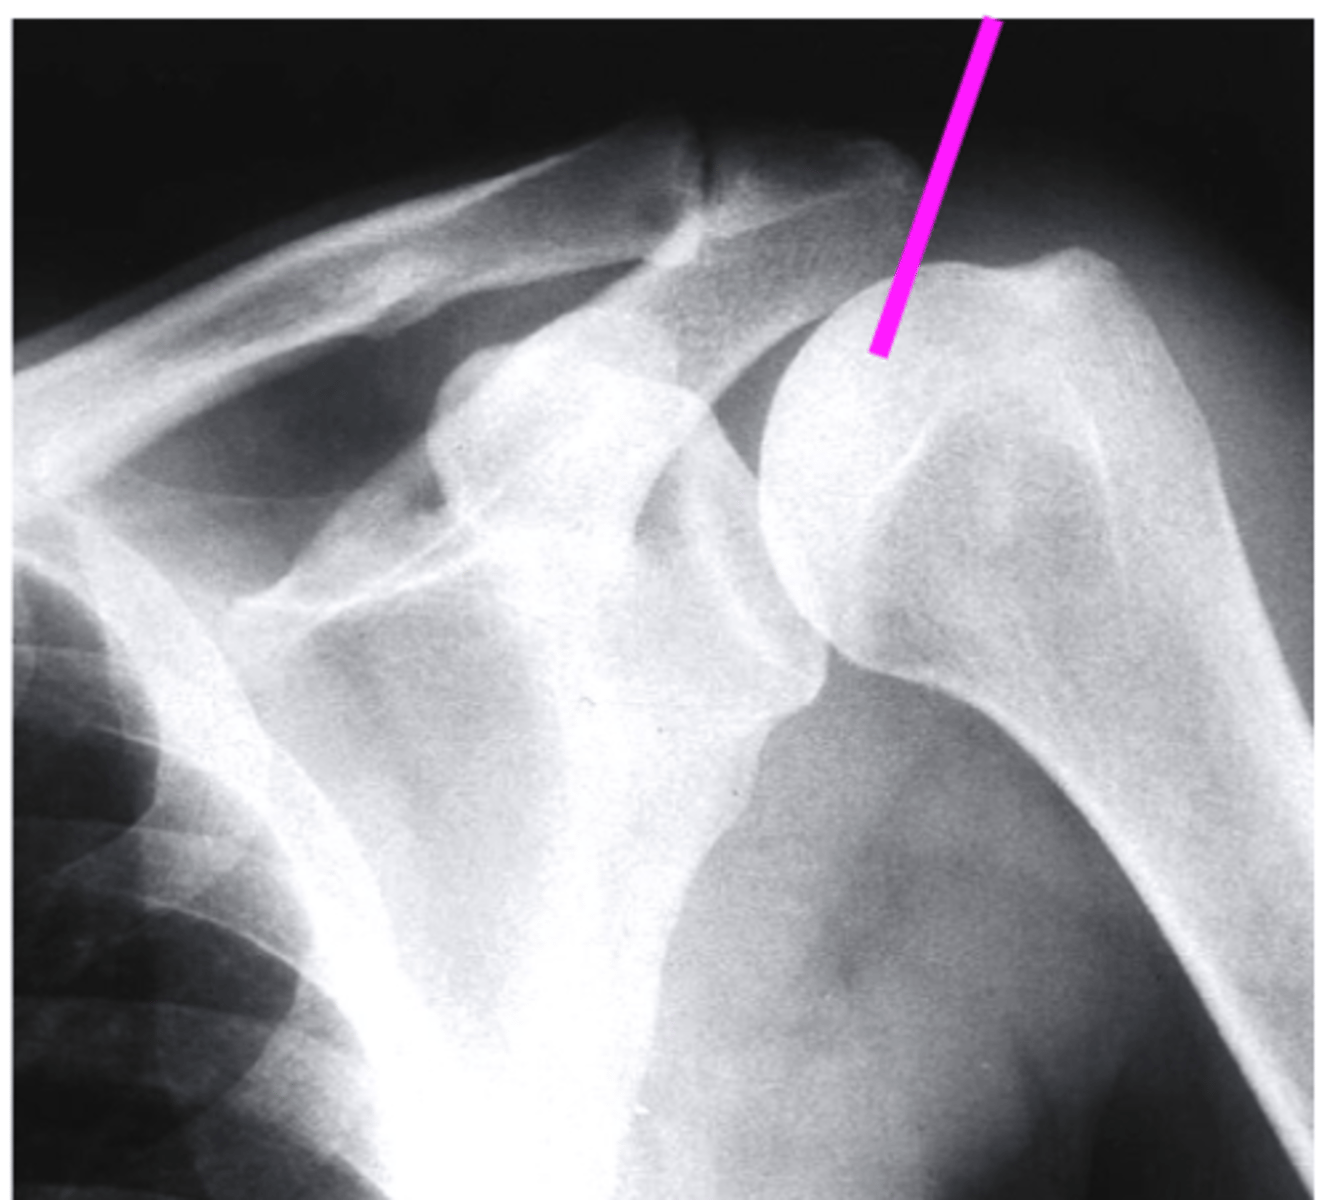

AP + ER

What view is this?

clavicle

what does the pink line point to?

spine of scapula

coracoid process

AC joint

acromion

Humeral Head

Greater Tuberosity

lesser tuberosity

Anatomic Neck of Humerus

Surgical Neck of Humerus

Shaft of Humerus

glenoid fossa

body of scapula

axillary border of scapula

vertebral border of the scapula